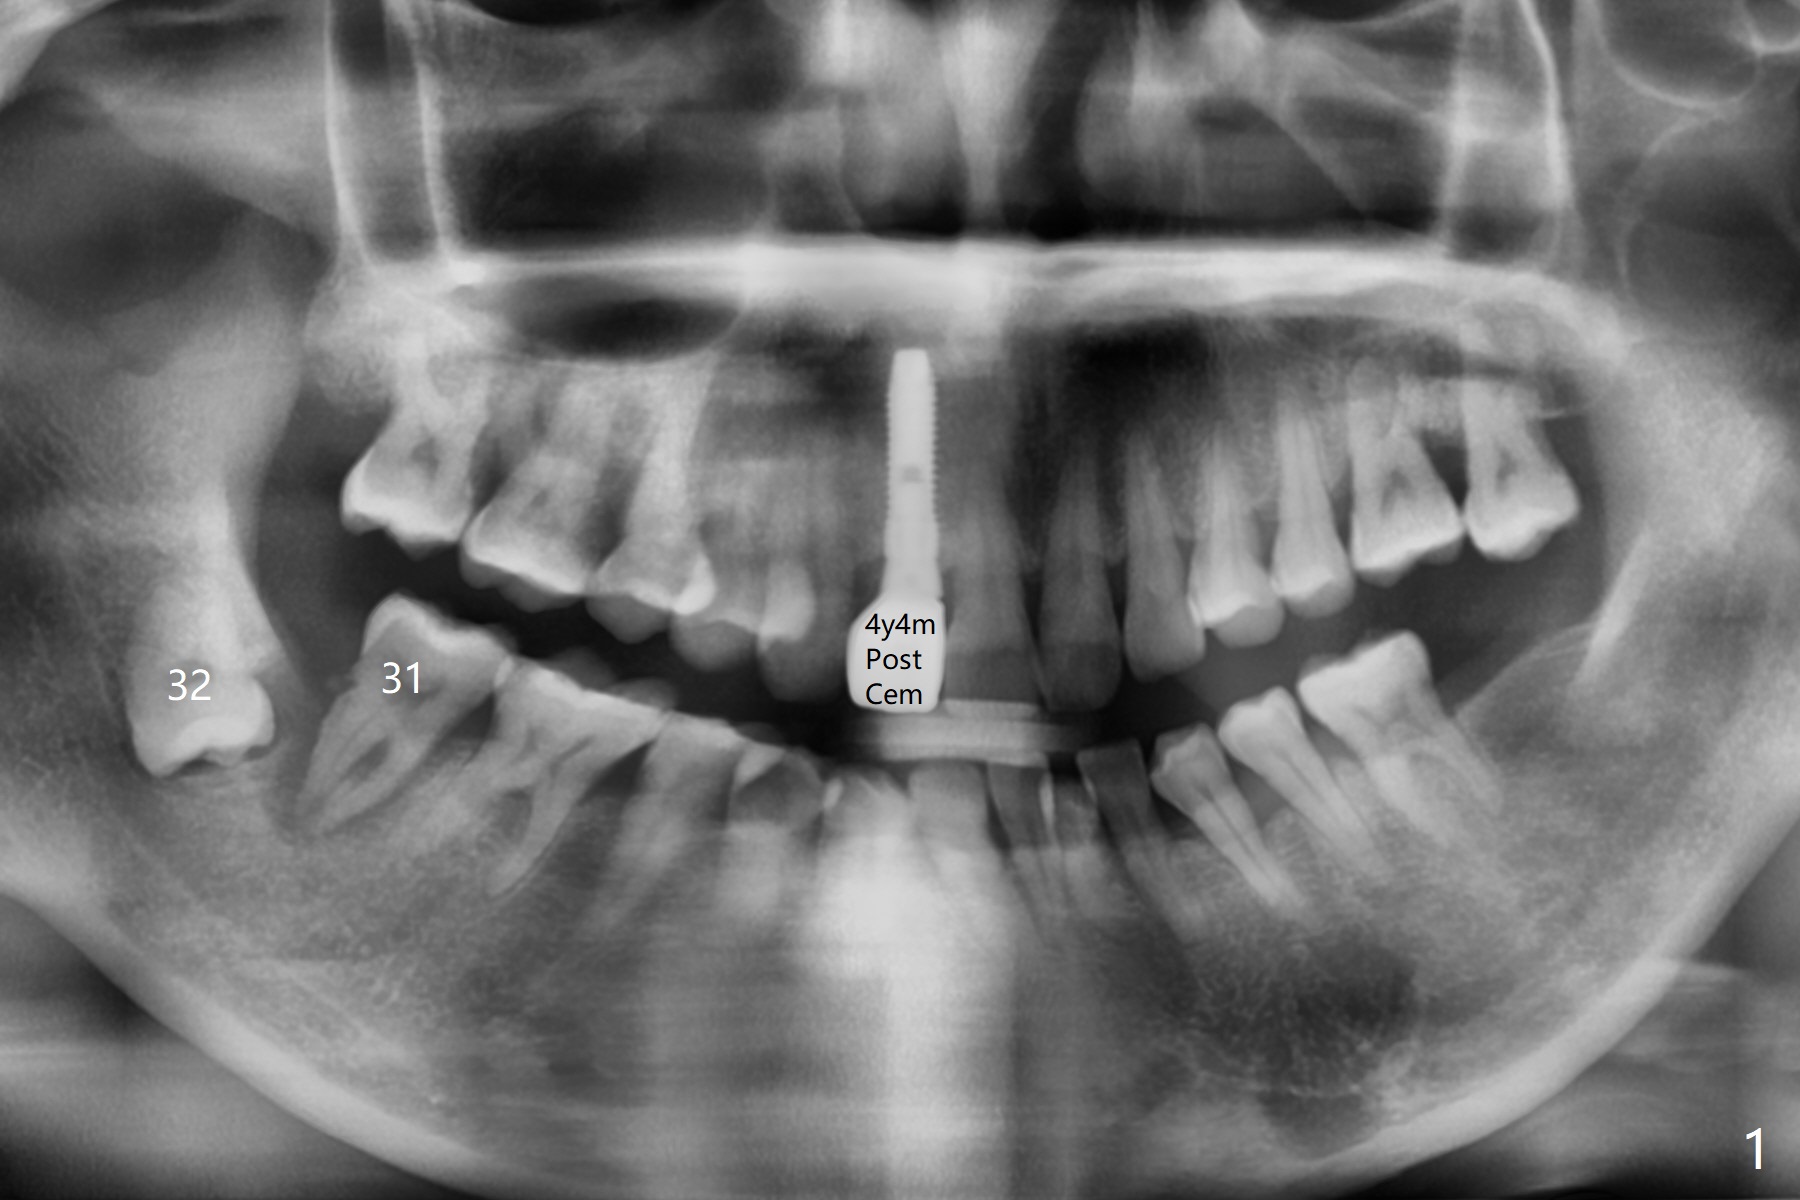

47岁女31号牙因严重牙周炎(图一)需要拔除导板即种大量植骨(图二)。炎症仿佛原发于31号牙(图二:*),为了减少创伤,选择不拔除32号牙,能行的通吗?